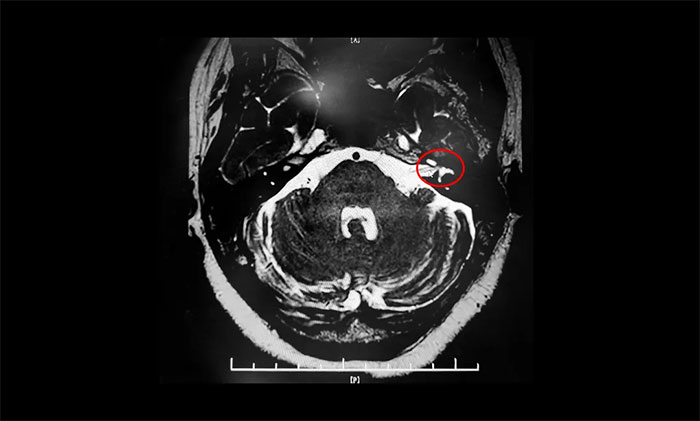

患者王阿姨左側(cè)眼面部抽搐10余年,以眼部最為明顯,偶有口角抽搐。起初,癥狀較輕,未引起重視,后病情加重才就醫(yī),經(jīng)藥物、針灸治療,無(wú)明顯效果。近兩年來(lái),癥狀持續(xù)加重,并影響睡眠。近日,王阿姨慕名求醫(yī)上海藍(lán)十字腦科醫(yī)院。面神經(jīng)MRTA檢查,結(jié)果示:左側(cè)面神經(jīng)與周?chē)⊙荜P(guān)系密切。確診面肌痙攣,手術(shù)指征明確。最終,楊忠旭博士順利為其行微血管減壓手術(shù)。

▲ 左側(cè)面神經(jīng)與周?chē)⊙荜P(guān)系密切